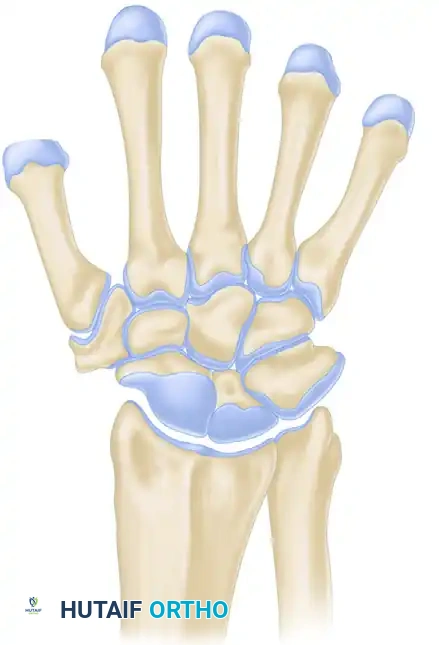

Pathoanatomy and Kinematics

The scaphoid serves as the critical mechanical link between the proximal and distal carpal rows. Its stability relies on a complex network of intrinsic and extrinsic ligaments. The primary stabilizer of the scapholunate articulation is the scapholunate interosseous ligament (SLIL), particularly its thick, robust dorsal subregion. Secondary stabilizers include the long radiolunate ligament and the radioscaphocapitate (RSC) ligament.

When these ligaments are disrupted, the synchronous motion of the proximal carpal row is lost. Biomechanically, the scaphoid has an inherent tendency to flex volarly, while the triquetrum has a tendency to extend dorsally. The lunate, caught in the middle, is normally balanced by these opposing forces.

Upon complete rupture of the SLIL and secondary stabilizers, the scaphoid rotates dorsally at its proximal pole and assumes a vertical, flexed orientation. Uncoupled from the scaphoid, the lunate follows the mechanical pull of the intact lunotriquetral ligament and extends dorsally. This divergent collapse pattern is clinically recognized as Dorsal Intercalated Segment Instability (DISI).